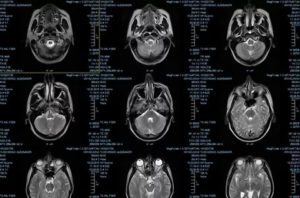

Результаты МРТ исследования врач-диагност получает в трехмерных срезных снимках мозга, а пациент получает изображение на носителе или на почту.

МРТ головного мозга здорового человека показывает целостный орган, без патологических очагов и смещений структур.

Описание заболеваний на сканировании:

МРТ при опухоли.

На снимке новообразование имеет вид несимметричного белого большого пятна, которое имеет рваные края. Это пятно может смещать соседние структуры головного мозга, из-за чего на снимке желудочки и пространства уменьшаются в размере. Когда растет опухоль, появляются новые сосуды. Это видно на ангиографической магнитной ангиографии.

Инсульты.

Ишемический инсульт – это область мозга, где недостает крови. Так, на снимке эта зона выделяется более светлым участком, в отличие от соседних зон. Однако в отличие от новообразования, это светлое пятно будет располагаться в области магистрального сосуда. Если применить ангиографию, то в области ишемии контрастирование снижается.

Геморрагический инсульт – это кровоизлияние в мозговое вещество. На снимке это выглядит как затемнение на МРТ в области магистральной артерии, окруженный темной полосой.

Болезни сосудов.

Расшифровка МРТ сосудов предоставляет следующие данные: в области атеросклероза снижается степень контрастирования; гипертоническая болезнь выявляется расширением дистальных периваскулярных областей; при аневризме сосуд утончен; мальформация на снимке представляется сосудами, которые располагаются по кругу и сходятся ближе к центру.